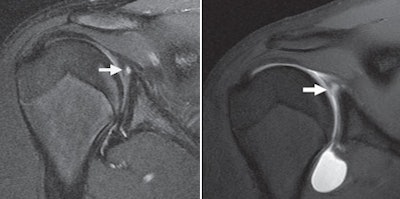

MRI can help, but it's also difficult to evaluate the condition of a labral tear and possibly avoid an unnecessary arthroscopy using only static images. Therefore, Magee set out to evaluate whether adding MR arthrography and the criterion of a 4-mm shift in a labral tear's position would help determine stability.

"The reason for using 4 mm as a cutoff is that this degree of motion shows a definite change in labral tear position ... and is considered indicative of an unstable tear," he wrote.

When unenhanced MR images were compared with MR arthrograms, 23 (28%) SLAP tears, 16 (30%) posterior labral tears, and 17 (40%) anterior labral tears had shifted 4 mm or more -- denoting instability. All patients with unstable labral tears proceeded to surgical tacking to correct the injury.